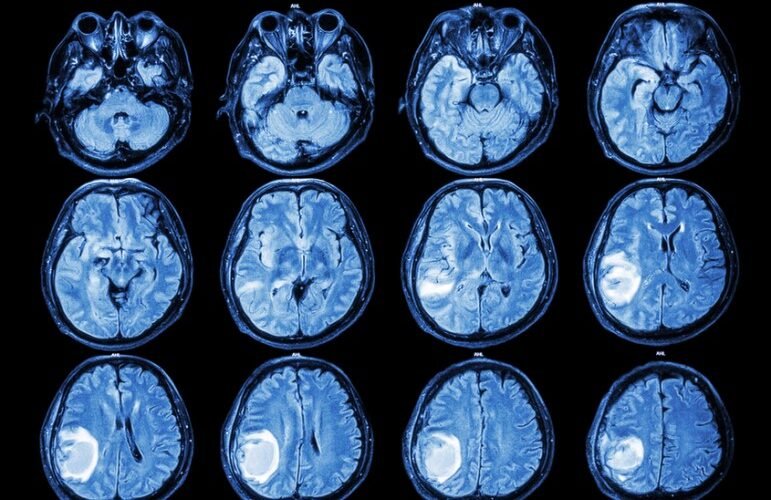

Le glioblastome , également appelé glioblastome polymorphe ou gliome de grade IV, est la tumeur cérébrale primaire maligne la plus courante et la plus agressive. Il représente 52% de toutes les tumeurs du tissu cérébral et il est très mortel: environ 50% des personnes diagnostiquées avec un glioblastome meurent dans l’année, tandis que 90% meurent dans les trois ans.